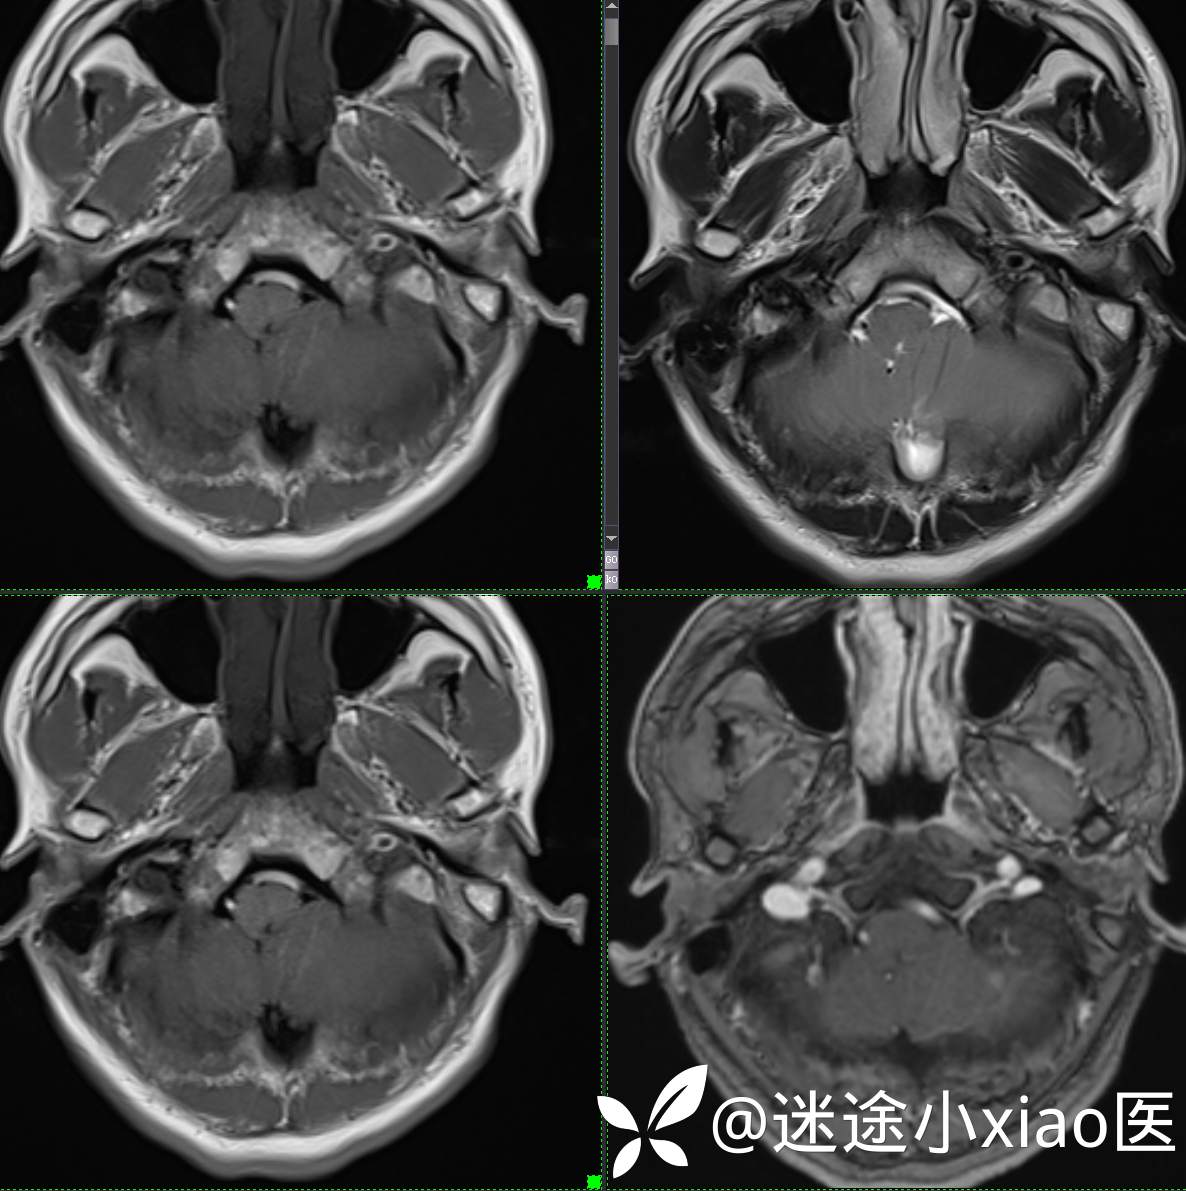

头颈组15:男,62岁,左侧小脑半球占位,原发?转移?是否有意外?

主 诉: 头晕、恶心呕吐半月余。

现病史: 患者半月前无明显诱因下明显头晕,伴恶心呕吐,无意识丧失、无智力明显下降,无视物模糊,无耳鼻腔出血,无四肢抽搐、畸形,无胸闷气促、呼吸困难。

既往:膀胱癌手术史。